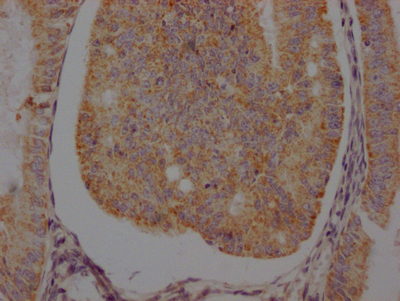

IHC image of CSB-RA286054A0HU diluted at 1:100 and staining in paraffin-embedded human endometrial cancer performed on a Leica BondTM system. After dewaxing and hydration, antigen retrieval was mediated by high pressure in a citrate buffer (pH 6.0). Section was blocked with 10% normal goat serum 30min at RT. Then primary antibody (1% BSA) was incubated at 4℃ overnight. The primary is detected by a Goat anti-rabbit IgG polymer labeled by HRP and visualized using 0.05% DAB.

IHC image of CSB-RA286054A0HU diluted at 1:100 and staining in paraffin-embedded human prostate cancer performed on a Leica BondTM system. After dewaxing and hydration, antigen retrieval was mediated by high pressure in a citrate buffer (pH 6.0). Section was blocked with 10% normal goat serum 30min at RT. Then primary antibody (1% BSA) was incubated at 4℃ overnight. The primary is detected by a Goat anti-rabbit IgG polymer labeled by HRP and visualized using 0.05% DAB.